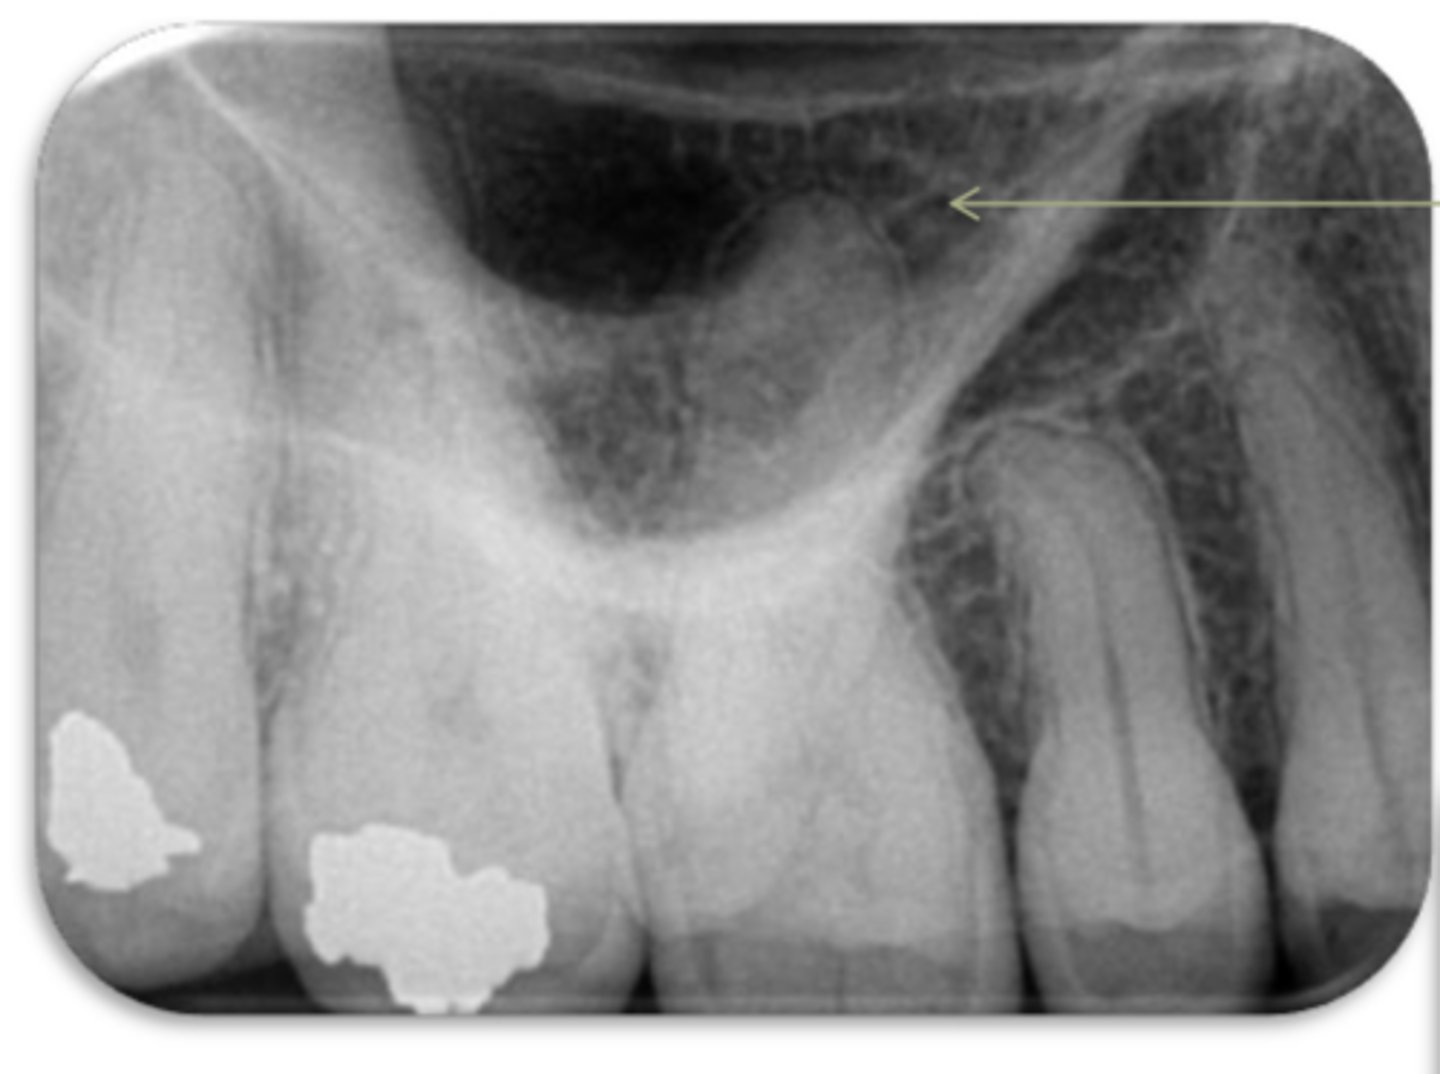

maxillary sinus

ID the structure: